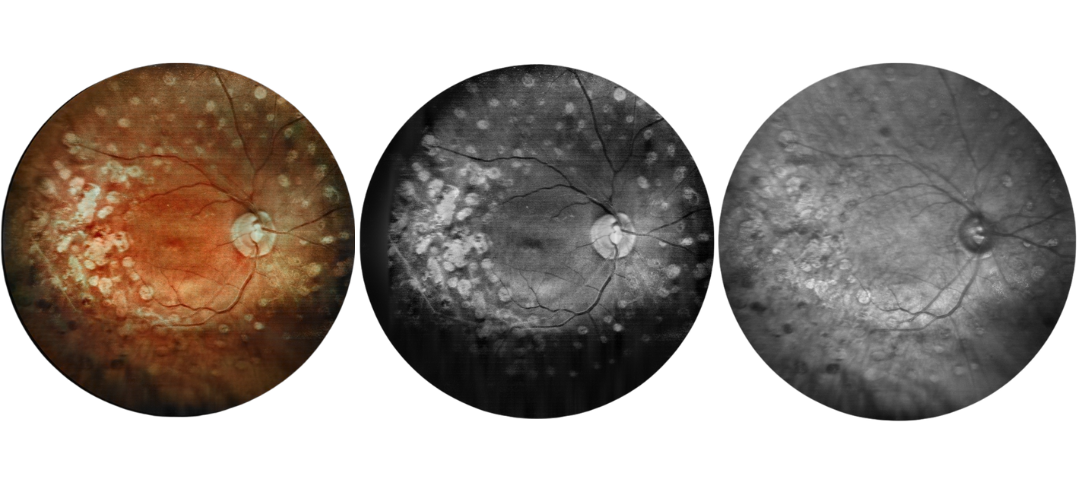

Fundus Cases Display

Our SLO makes fundus examination easier for you, capturing ultra-clear and wide-angle images of the retina and choroid, and then synthesizing color fundus images to present a rich picture of the fundus status.

Diabetic retinopathy: post photocoagulation

Diabetic retinopathy: bleeding, exudation, and post-photocoagulation

Diabetic retinopathy: bleeding and exudation

Diabetic retinopathy: bleeding, exudation and choroidal vascular abnormalities